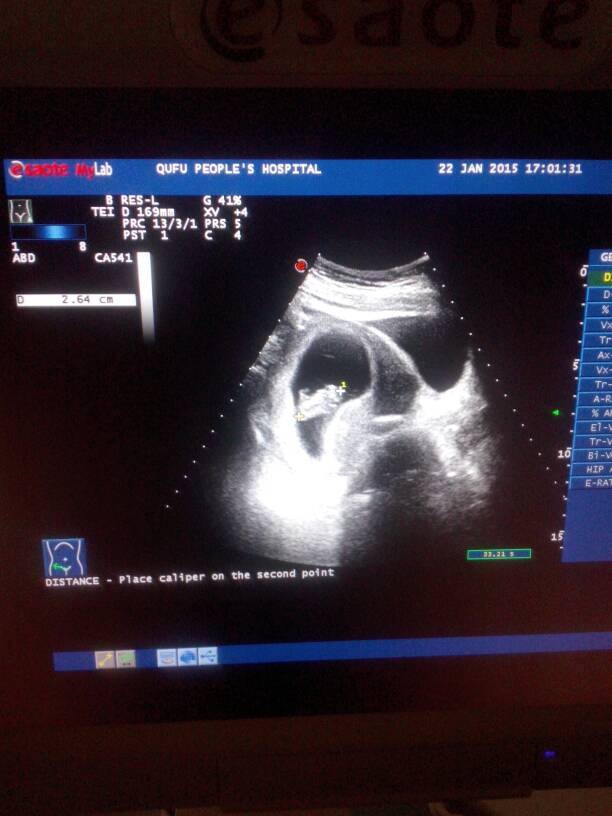

16周+B超单10周彩超图求大神鉴别男宝女宝 16周+B超单10周彩超图求大神鉴别男宝女宝 点击展开 拉线哥 2015-03-11 22:29 为您推荐: 其他回答 我直觉你宝宝是男娃娃 183*****294 2015-03-12 07:43 不会看啦! 旺旺喵 2015-03-12 05:20 男孩子。。 183*****294 2015-03-11 23:28 嗯嗯 我的宝宝很大18周了 看的很清楚 鸿爷的麻麻 2015-03-11 22:57 而且很大? 鸿爷的麻麻 2015-03-11 22:49 加载更多 相关问题 为什么27周照的四维彩超图还不清楚 这么模糊呢? 请问怀孕几周去检查单胎双胎,做彩超图啊 今天做了彩超图,10+5周,头臀径38,孩子是正常不,宝妈们帮我看看,谢谢了